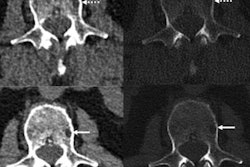

Inoue and colleagues sought to assess photon-counting CT's impact on radiologist confidence in the diagnosis of interstitial pneumonia when compared with conventional CT technology. The team conducted a study that included 30 patients with suspected interstitial lung disease (median age, 69) all of whom underwent CT on a conventional scanner as well as a photon-counting CT system.

Photon-counting CT improved the diagnostic confidence of the study readers for a number of imaging findings and increased overall image quality at lower radiation doses. (Conventional CT had a radiation dose of 7.88 mGy compared with 6.49 mGy for photon-counting CT, with a p-value of less than 0.001.) The team also found good intraobserver agreement (values between 0.75 and 0.9) for imaging findings such as reticulation, honeycombing, and the possibility of interstitial pneumonia.

"Photon-counting CT increased radiologist confidence in the presence of key imaging finding indicating usual interstitial pneumonia -- for example, reticulation -- or a diagnosis other than usual interstitial pneumonia [through findings such as ground glass opacities or mosaic attenuation]," Inoue said. "And early detection of fibrosis in the lung parenchyma depicted as reticulation could contribute to timely intervention via an antifibrotic agent."

"Photon-counting detector CT provides improved image quality that translates into increased diagnostic confidence in reticulations, mosaic pattern, and ground glass opacities, which may improve imaging diagnosis of usual interstitial pneumonia," Inoue concluded.